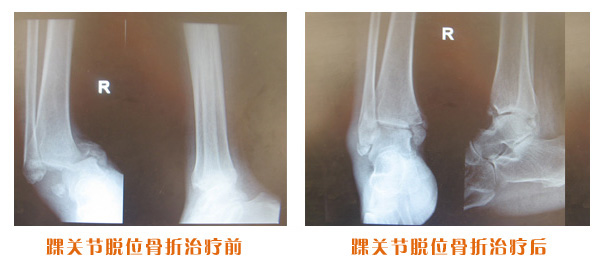

肥城市安駕莊梁氏骨科醫(yī)院是一所以梁氏手法正骨配合膏藥為特色的現(xiàn)代化專科醫(yī)院。

梁氏骨科術(shù)始創(chuàng)于清雍正年間,歷經(jīng)八代,至今已有三百年歷史。據(jù)1929年泰安縣志載“梁瑞圖先生,字增生,號(hào)蓮峰,安駕莊人,精岐黃并發(fā)明接骨,凡跌打車凡跌打車軋皮不破而碎骨者......【詳細(xì)】 |